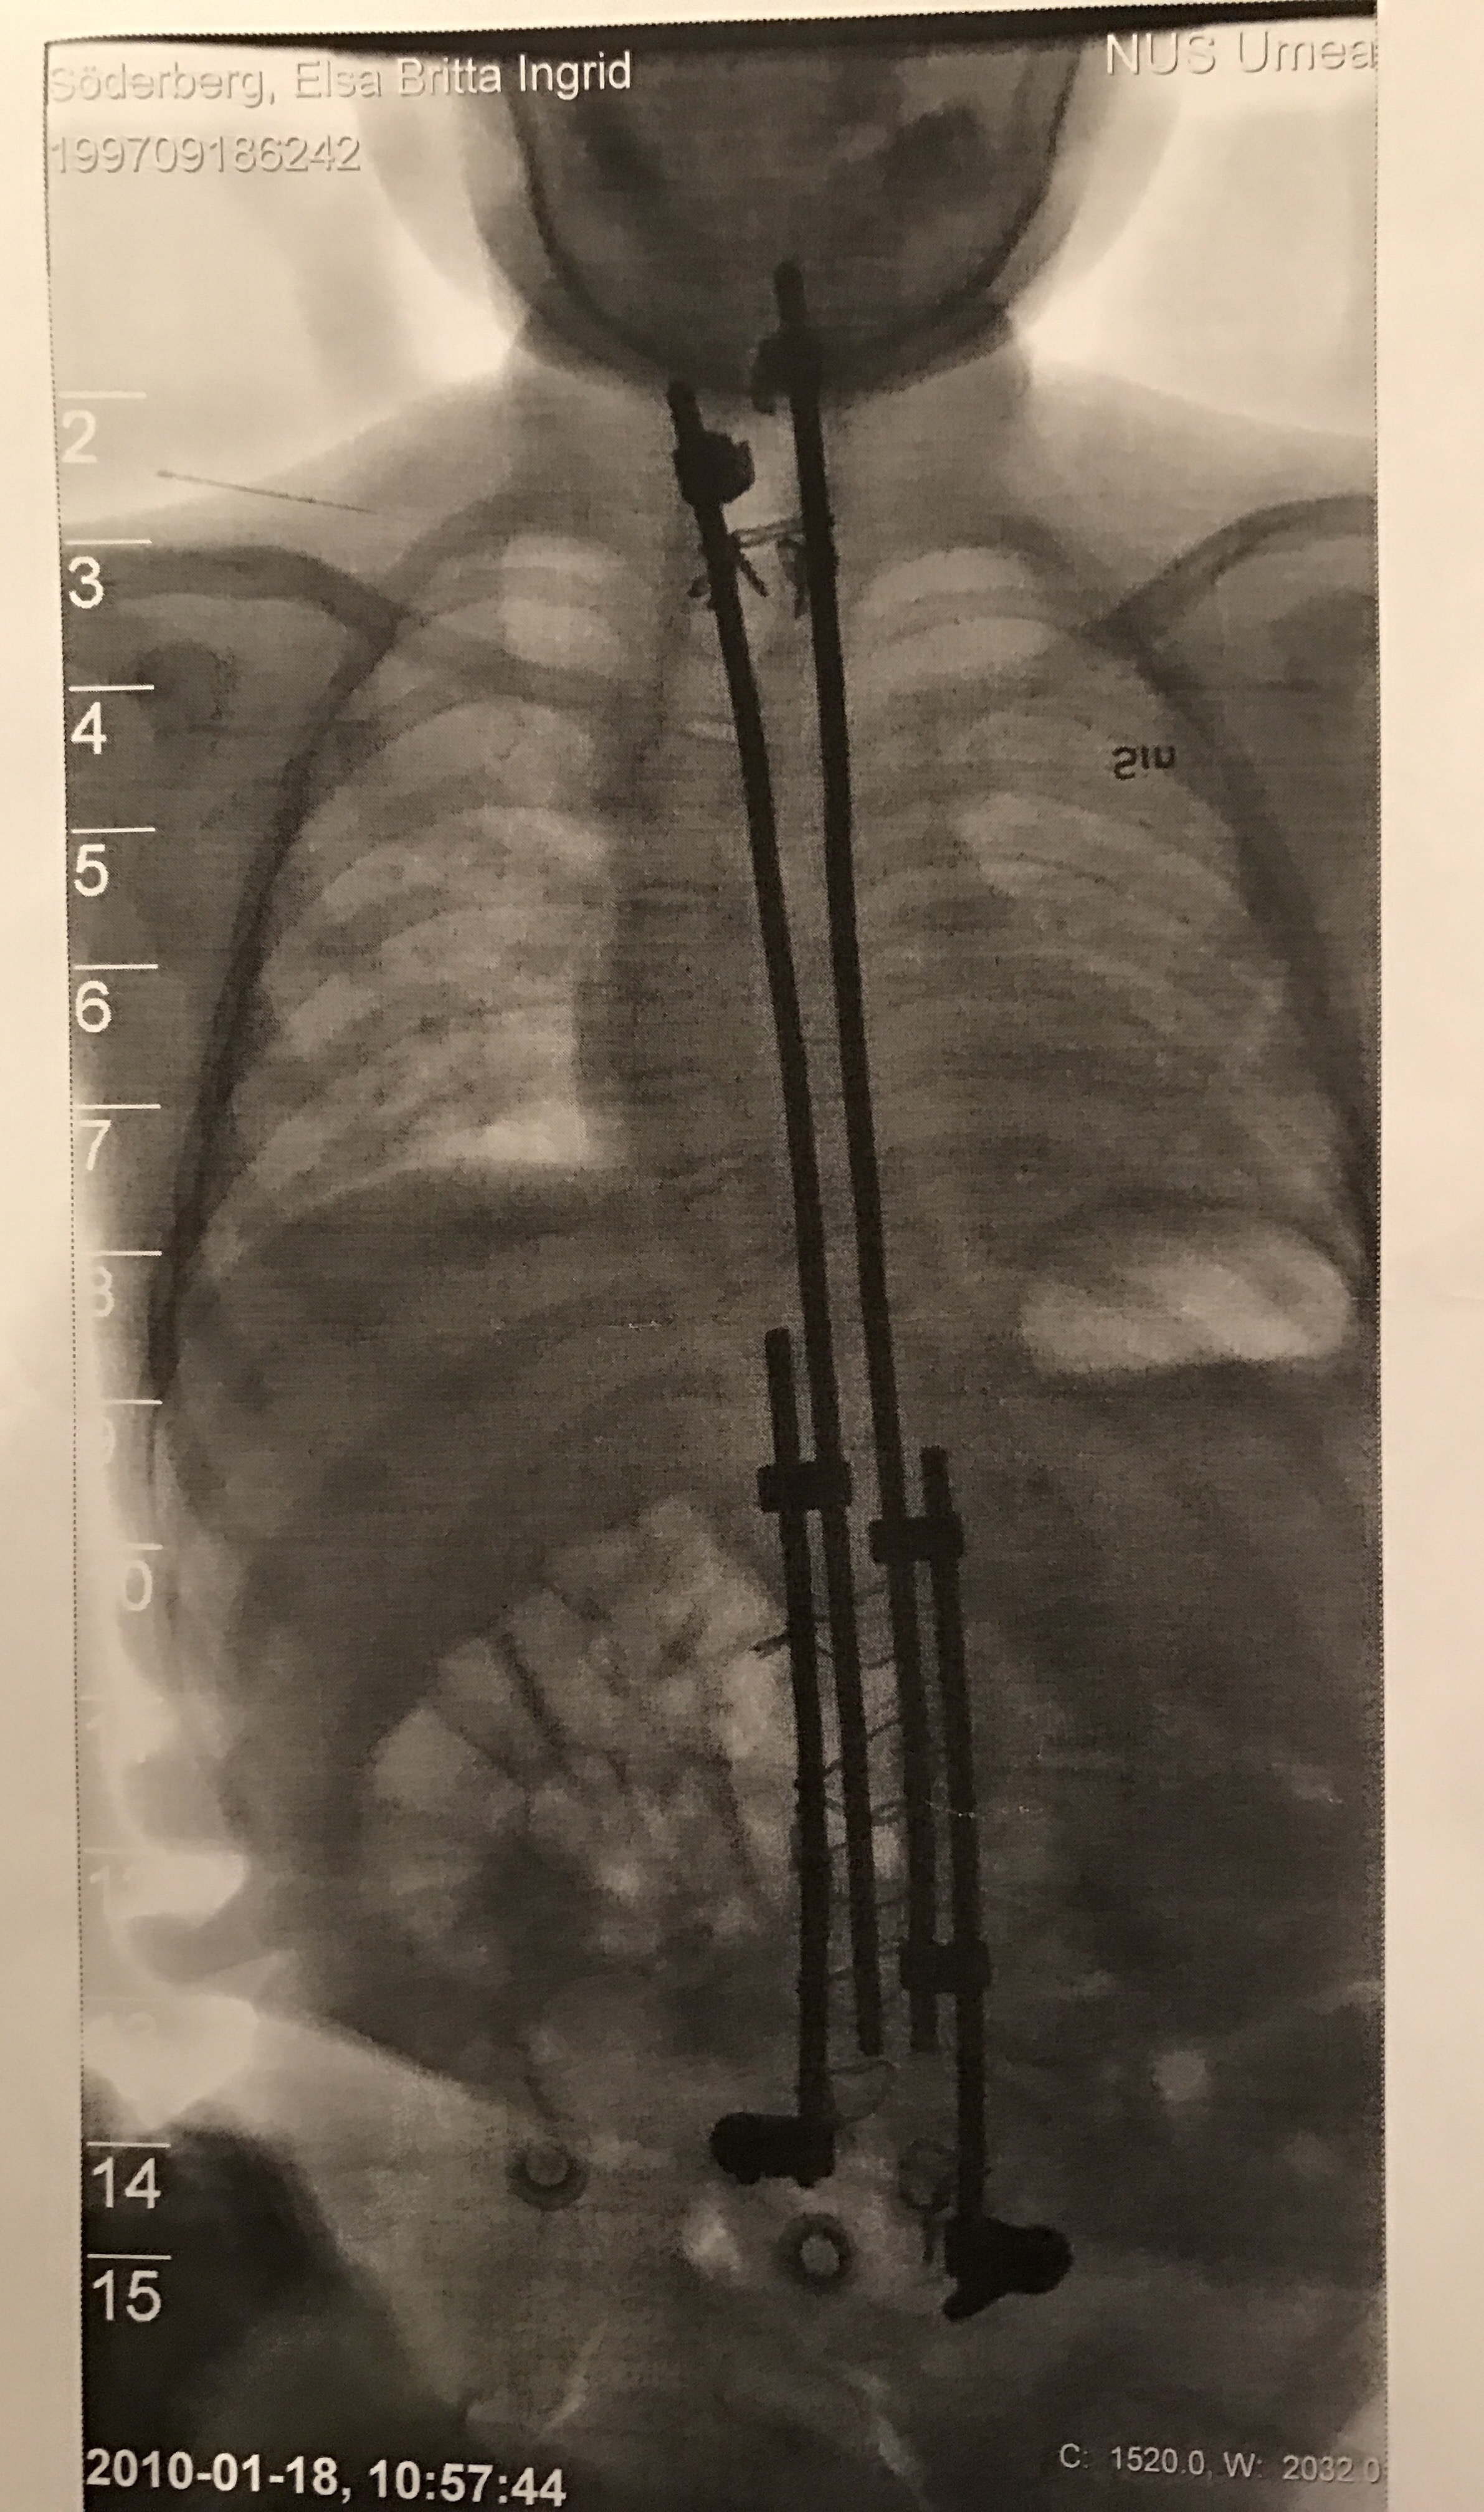

För att lungorna skulle få plats att växa så kunde ingen steloperation göras på en gång utan en typ av stag skulle skruvas fast på några ställen av ryggraden,stagen skulle sedan förlängas genom en operation varje halvår tills ryggen blivit tillräckligt lång.

När det gått et halvt år får vi en kallelse då läkaren funderar på att göra den första stagförlängningen.

Vi måste vänta,men det görs ytterligare tre förlängningar med komplikationer ,fast inte så kraftiga som den första .